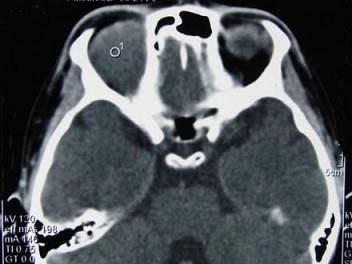

问题 男,12岁,有脓涕数年,发热约十天,伴右眼球向外下突出,CT如图,应诊断为 ( )

选项 A、眼型Graves病 B、肌炎型炎性假瘤 C、骨髓炎 D、骨膜下脓肿 E、转移瘤

答案 D